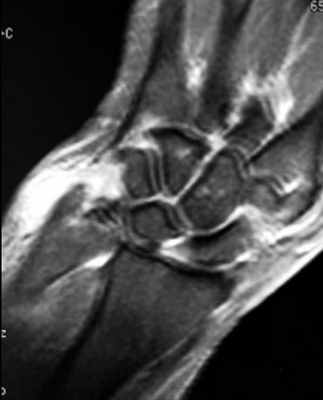

Результат МРТ правого лучезапястного сустава (рис. 2), подтвердил клиническое предположение о повреждении ладьевидно-полулунной связки, который заключался в нарушении целостности структуры связки. Также были выявлены признаки асептического некроза ладьевидной кости в стадии отека костной ткани.

Рис. 2. МРТ-исследование правого лучезапястного сустава. Получены протон взвешенные изображения с подавлением сигнала от жировой ткани (PD FAT SAT) в аксиальной, сагиттальной и фронтальной плоскостях, Т1 взвешенные изображения во фронтальной плоскости. На полученных сканах определяется: 1 – увеличение ладьевидно-полулунного сустава вдвое по сравнению с соседними; 2 – вдоль оси ладьевидной кости отмечается скопление жидкости, что можно расценить, как продольный перелом ладьевидной кости, либо отек костной ткани